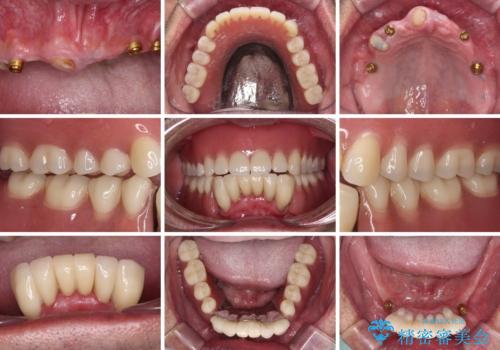

どこで咬んでいいのか分からない インプラント・オーバーデンチャーによる補綴治療

全顎的にインプラント補綴を行うことも検討しましたが、費用面から、インプラントを土台とした入れ歯(インプラント・オーバーデンチャー)による補綴治療を行うこととしました。

入れ歯の固定源にはマグネットやロケーター、ボールアタッチメントなどがありますが、お住まいが遠方であることや、奥歯に力がかかりやすいことから、維持力が強く、メインテナンスが行いやすいロケーターを採用しました。